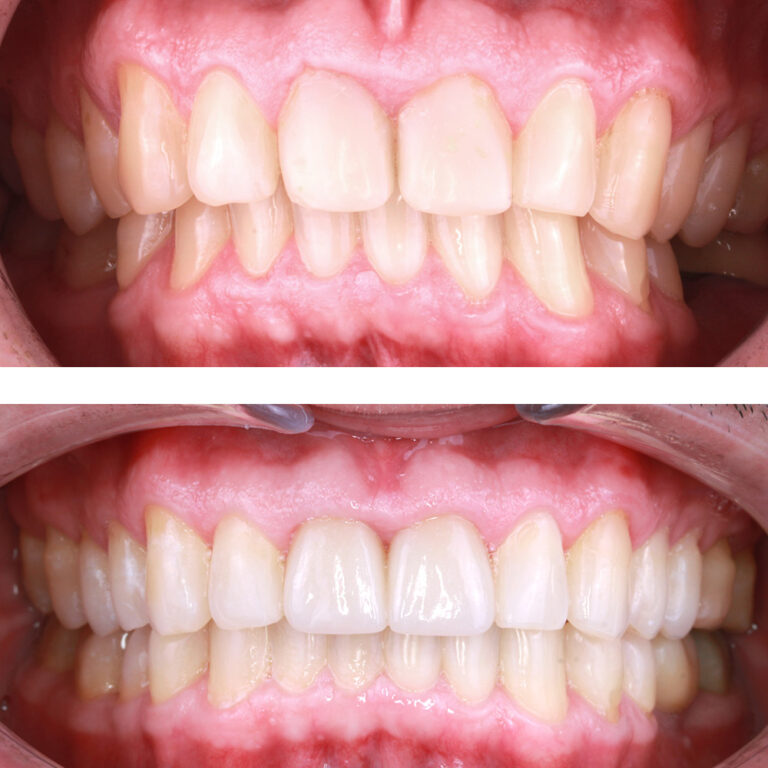

Кейс 12

Бирковская Екатерина Александровна

Количество кап ВЧ 24

Количество кап НЧ 41

ДО

ПОСЛЕ